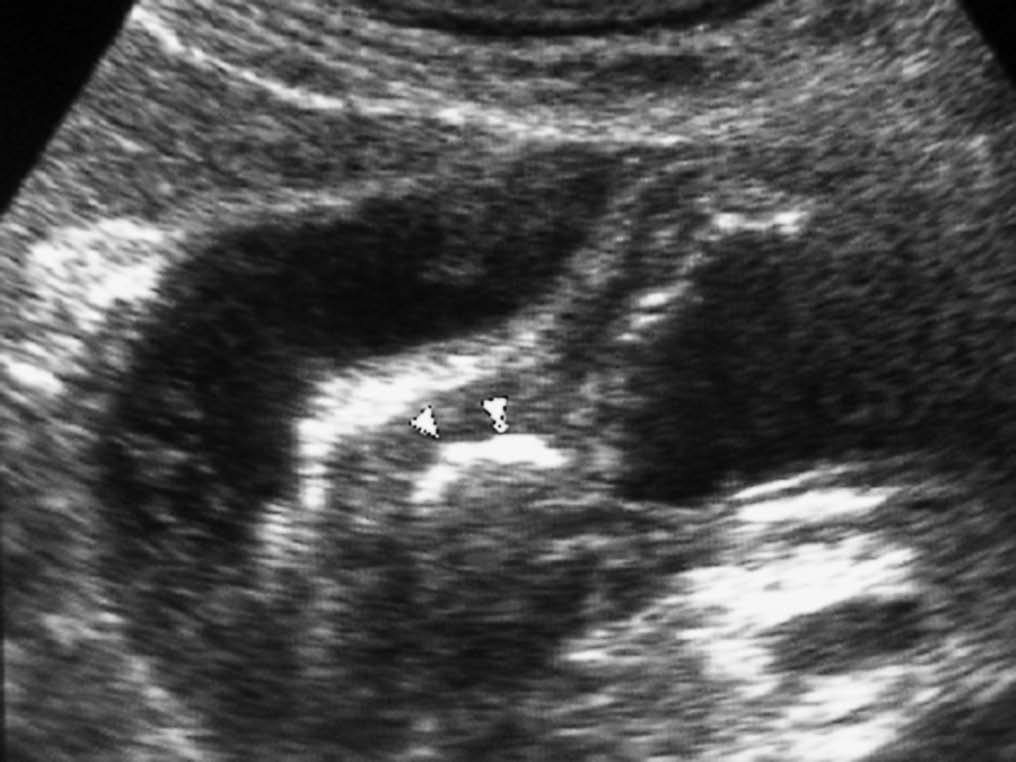

El linfoma intestinal también asienta con mayor frecuencia en el íleon. Aparece como un engrosamiento de pared, a veces nodular, que puede ser focal o difuso, que característicamente no produce estenosis de la luz intestinal, pudiendo producir una dilatación aneurismática del segmento afectado. La presencia de adenopatías viscerales o retroperitoneales, así como esplenomegalia puede sugerir el diagnóstico (fig. 20)22,24. Los tumores estromales malignos pueden alcanzar un tamaño considerable, apareciendo en la TC como masas heterogéneas con zonas internas hipodensas, debido a su tendencia a la necrosis y hemorragia, con realce periférico de contraste. Los malignos pueden invadir órganos vecinos, diseminarse al peritoneo o dar metástasis hepáticas, pero no suelen asociar adenopatías21,25,26.

Fig. 20--Linfoma duodenal. (A) Ecografía. (B) Tomografía computarizada con contraste intravenoso que muestra un engrosamiento circunferencial de la pared duodenal (D) con adenopatías mesentéricas y retroperitoneales (flechas).